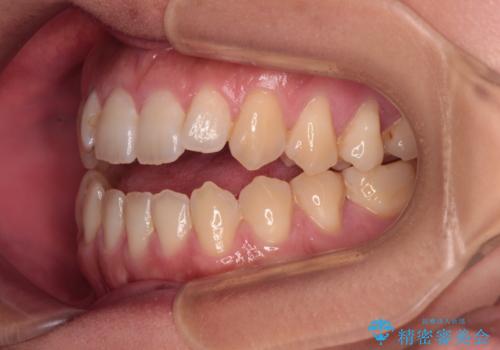

【モニター】食事が取りづらい 極端な開咬をインビザラインで解決

- 極端な開咬を気にして来院された患者様です。

開咬の方の特徴として、幼少期の指しゃぶりの癖や、強い舌の突出癖が挙げられます。

こちらの患者様も強い舌の突出癖が認められたため、矯正治療を行うにあたり、舌のトレーニングをしっかりと行っていただくように指示をいたしました。

開咬はインビザラインが得意とする歯列不正であるため、舌のトレーニングを行いながら、インビザラインにて矯正治療を行うこととしました。

担当医としては、もっと上下の前歯を接触させるところまで治療を進めたいという思いがありますが、今まで咀嚼できなかったものが食べられるようになったということで、この状態で治療終了となりました。